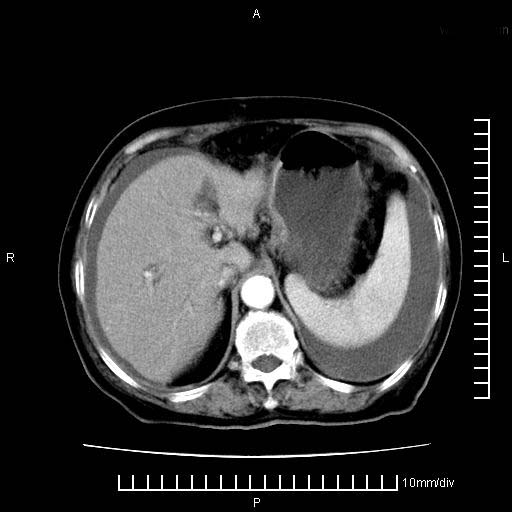

标题: CT28280:腹部增强:女性,80岁

上腹疼痛月余,外院核磁诊断胰腺癌。现临床示右下腹可明显触及包块,可片子上怎么没有看到?

2。腹腔积液。

1。胰腺ca伴腹膜腔转移

2。肝左叶低密度灶,考虑转移可能

支持胰腺癌肝内转移,腹水改变。

1、考虑胰腺癌伴腹膜腔转移,胸腹水。

2、肝脏转移可能。

1)考虑胰腺癌并胰腺假性囊肿形成。2)肝内低密度灶,不排除转移。3)右肾盂积水。4)腹水。5)右侧胸腔积液并右肺下叶部分膨胀不全。